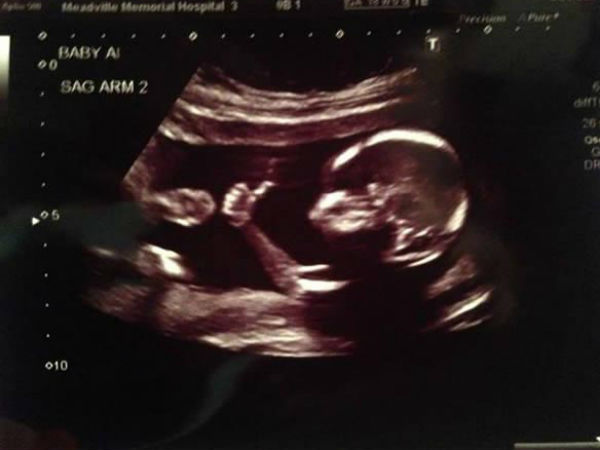

வயிற்றில் இருக்கும் குழந்தை :

மெலிசாவின் தாய் கர்ப்பமாக இருந்த போது தன்னுடைய மூன்றாவது ட்ரைம்ஸ்டரில் குழந்தை வேண்டாம் என்று முடிவெடுக்கிறார். இந்த குழந்தையை கருக்கலைப்பு செய்துவிட வேண்டும் என்று முடிவெடுத்து மருத்துவமனைக்குச் செல்கிறார்.

அங்கே அனுமதிக்கப்பட்ட அவருக்கு ஐந்து நாட்கள் ட்ரிப்ஸ் ஏற்றப்படுகிறது. அதிலிருக்கும் மருந்துகளால் வயிற்றில் இருக்கும் குழந்தை இறந்துவிடும் என்று நினைத்து இருக்கிறார்.

பக்கெட்டில் குழந்தை :

குழந்தை இறப்பதற்கு பதிலாக அவருக்கு பிரசவ வலி உண்டானது.அழகான பெண்குழந்தையை பெற்றெடுத்தார்.

வேண்டாம் என்று நினைத்து விஷம் கொடுக்கப்பட்ட குழந்தை எப்படியும் இறந்திருக்கும் என்று நினைத்து அந்த குழந்தையை பார்க்காமல் மருத்துவமனையில் இருந்து வெளியேறிவிட்டார்.

அந்த மருத்துவமனையில் அபார்சன் செய்யப்பட்ட குழந்தையை ஒரு பக்கெட்டில் போட்டு வைக்கும் நடைமுறை இருந்திருக்கிறது. அதே போல மெலிசாவையும் போட்டு வைத்தார்கள்.

உயிர் பிழைத்த அதிசயம் :

அம்மா தன்னை கொல்வதற்காக உட்கொண்ட எல்லா விஷத்தையும் ஏற்றுக் கொண்டும் உயிரை விடாமல் உயிருக்காக போராடிக் கொண்டிருந்த மெலிசாவின் முனகல் சத்தம் அங்கிருக்கும் செவிலியர் காதுக்கு எட்டியிருக்கிறது.

உடனடியாக அவசர சிகிச்சை பிரிவிற்கு கொண்டு செல்லப்பட்ட மெலிசாவிற்கு நுரையீரலில் பிரச்சனை.அதனால் மூச்சு விடுவதற்கு திணறிக்கொண்டிருந்தது அந்த குழந்தை.

தீவிர சிகிச்சைக்குப் பிறகு அந்த குழந்தை உயிர் பிழைத்துக் கொண்டது.